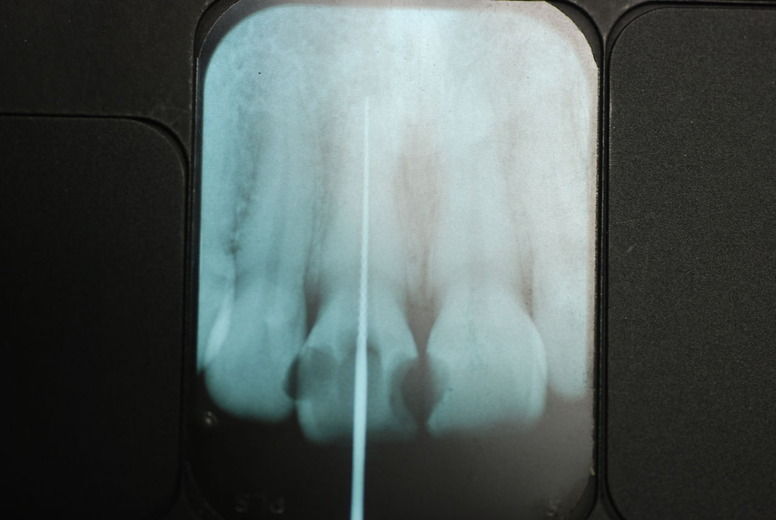

14年歯前、歯の神経が腐り、神経を除去したまま来なくなった現在大学生の女性

歯周病になっていましたが、少し色が黄色くなっているだけで比較的綺麗な歯の状態です。

平成9年来院神経を取り、同時に歯周病の話をしてそのまま来なくなっていたかたですが、たまたま一部欠けてきました。それで来院。

平成9年![40af2ca7-s[1]](https://livedoor.blogimg.jp/netdental/imgs/0/d/0d02b3dc.jpg)